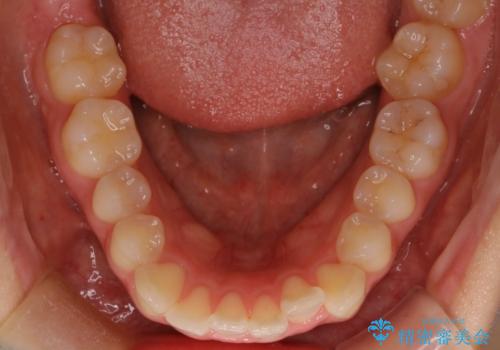

下顎前歯の叢生を短期間で改善

- 患者様は、下顎前歯のガタガタ(叢生)の改善を希望して来院されました。診断の結果、非抜歯で治療可能であると判断し、透明で目立たないインビザラインを使用する矯正治療計画を立案しました。短期間での治療を希望されていたため、IPR(歯間削合)を併用してスペースを確保しながら、効率的に歯を並べることを目指しました。

治療では、インビザラインを用いて計画的に歯を移動させ、短期間での歯列改善を実現しました。IPRを行うことで、抜歯をせずに必要なスペースを確保し、歯列全体を整えました。治療中は、装置の適切な装着時間を守ることが重要であり、患者様にも継続的な協力をお願いしました。また、歯肉や歯根への負担を最小限に抑えるため、歯の移動を慎重に管理しました。結果として、短期間で下顎前歯の叢生を改善し、自然な見た目と機能性を兼ね備えた歯列を実現できました。